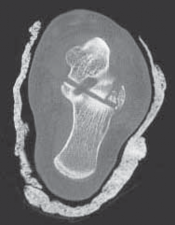

A B C TECH FIG 3 • A. Bone model depicting talar neck and dome fracture (AP view). B. Bone model depicting talar neck and dome fracture (lateral view). C. CT image of coronal talar body fracture.

Displaced, intra-articular posterior talar body fractures present largely in the coronal plane ( TECH FIG 4).